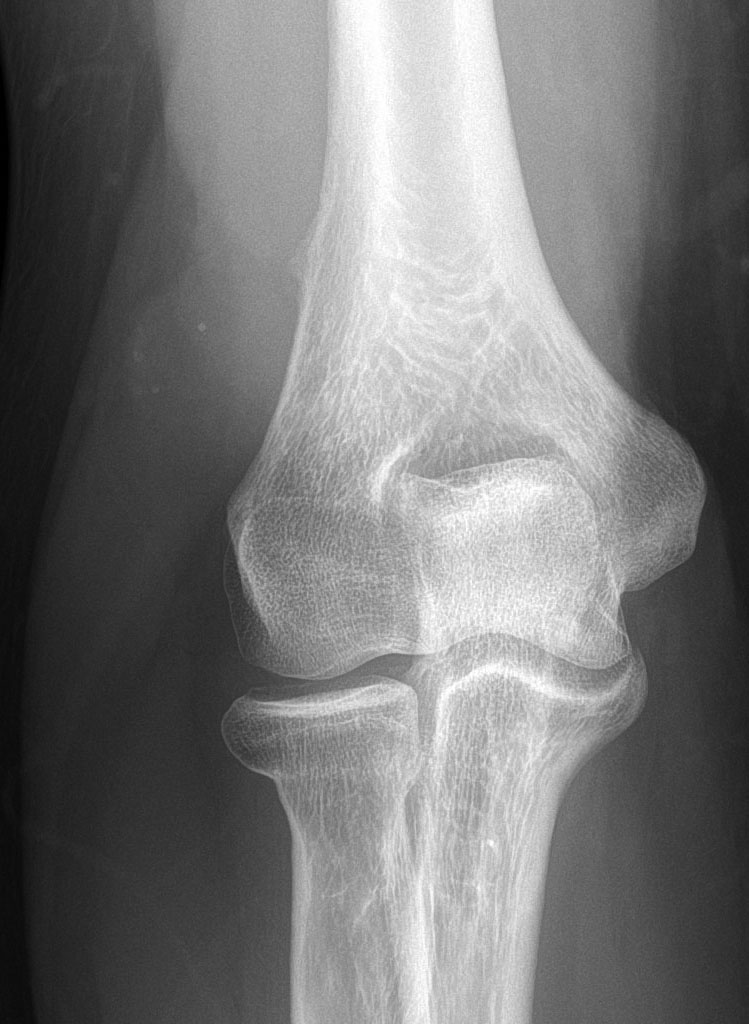

#CaseOfTheWeek‼️🥳‼️ ☢️🩻☠️Case#22☠️🩻☢️ #Mass 📲➡️➡️#Diagnosis❔❓❔ #FOAMRad #RadEd #MedEd #OrthoEd #OrthoTwitter @ssr_rwg @UWRadRes @ISSVA_org